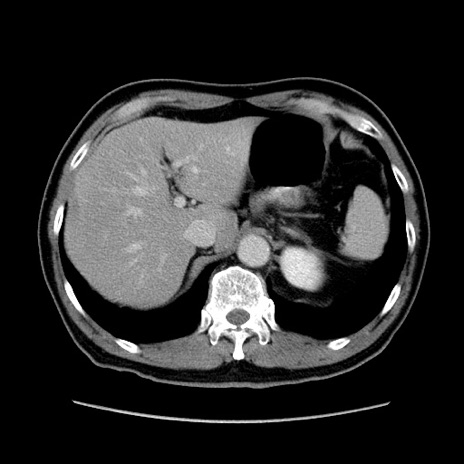

症例34(横断像)

【症例】60歳代 男性

【主訴】右鼠径部膨隆

【現病歴】1年程前より右鼠径部膨隆あり。自己にて還納可能だったため放置していた。3時間前より右鼠径部の脱出を認め、還納困難となり受診。

【既往歴】高血圧

【身体所見】右鼠径部に小児頭大の膨隆あり。弾性硬であり、用手還納は困難。左鼠径部にも膨隆を認める。脱出はなし。

【データ】WBC 15500、CRP 測定なし